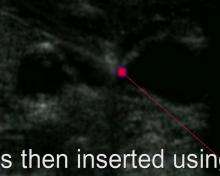

Insertion

Before insertion, the patient is first assessed by reviewing relevant labs and indication for CVC placement, in order to minimize risks and complications of the procedure. Next, the area of skin over the planned insertion site is cleaned. A local anesthetic is applied if necessary. The location of the vein is identified by landmarks or with the use of a small ultrasound device. A hollow needle is advanced through the skin until blood is aspirated. The color of the blood and the rate of its flow help distinguish it from arterial blood (suggesting that an artery has been accidentally punctured). Within North American and Europe, ultrasound use now represents the gold standard for central venous access and skills, with diminishing use of landmark techniques.[20][21] Recent evidence shows that ultrasound-guidance for subclavian vein catheterization leads to a reduction in adverse events.[22]

The line is then inserted using the Seldinger technique: a blunt guidewire is passed through the needle, then the needle is removed. A dilating device may be passed over the guidewire to expand the tract. Finally, the central line itself is then passed over the guidewire, which is then removed. All the lumens of the line are aspirated (to ensure that they are all positioned inside the vein) and flushed with either saline or heparin.[1] A chest X-ray may be performed afterwards to confirm that the line is positioned inside the superior vena cava and no pneumothorax was caused inadvertently; electromagnetic tracking can be used to verify tip placement and provide guidance during insertion, obviating the need for the X-ray afterwards.